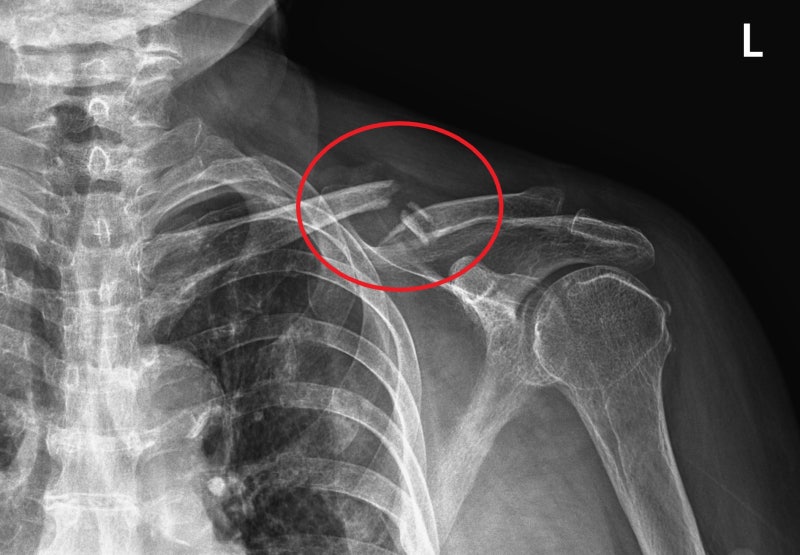

สาเหตุสำคัญที่ทำให้เครื่องดื่มบางชนิดถูกมองว่า “ทำลายกระดูก” มักเกี่ยวข้องกับส่วนประกอบ เช่น น้ำตาลในปริมาณสูง คาเฟอีน หรือกรดฟอสฟอริก สารเหล่านี้อาจรบกวนการดูดซึมแคลเซียมของร่างกาย หากบริโภคต่อเนื่องเป็นเวลานาน ร่างกายอาจสูญเสียแร่ธาตุที่จำเป็นต่อความแข็งแรงของกระดูก โดยเฉพาะในกลุ่มวัยรุ่น วัยทำงาน และผู้สูงอายุที่ต้องการแคลเซียมอย่างเพียงพอเพื่อเสริมสร้างและคงสภาพมวลกระดูก